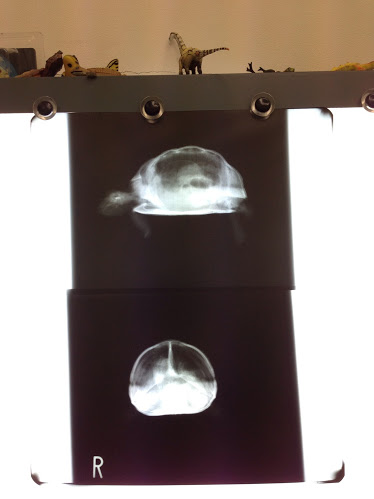

上:横から見たところ(左が頭)、下:正面から見たところ

素人目に見ても嫌な感じがしました。

ハッピーのときのレントゲン写真とは違い、白い部分が多いです。

先生の話を聞くとどうやら肺炎ではないらしい。

しかし気管支炎との診断が・・・

どうも、気管支炎のため空気が肺に100%入らずに胃などへ流れて溜まってしまっているみたいです。

写真の左側の白い面積が広いと思いますが、ここにガスが溜まっているみたいです。

100%の空気が肺に入らないためさぞ苦しかったと思います。